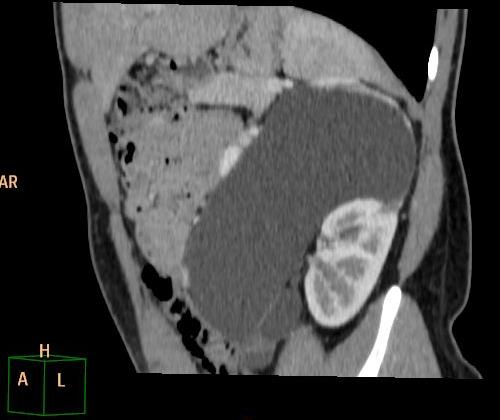

Pacjentka została przyjęta do Szpitala, wykonano nieskuteczną próbę odgłobienia wlewem wodnym pod kontrolą USG (biała strzałka - wgłobienie, pomarańczowe strzałki - płyn w jelicie grubym). Pacjentka operowana - stwierdzono wgłobienie patologiczne, z uchyłkiem Meckela jako punktem prowadzącym.